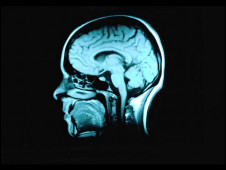

接受教育可降低患失智癥風(fēng)險(xiǎn)

接受教育越高的人越能適應(yīng)大腦老化帶來的問題。

科學(xué)家發(fā)現(xiàn)受教育時(shí)間越久,出現(xiàn)失智癥的機(jī)率就越低。

在過去10年當(dāng)中,有關(guān)失智癥(dementia, 或稱癡呆)的各項(xiàng)研究一致顯示接受教育的時(shí)間越長的人,患失智癥的機(jī)會(huì)越低。

現(xiàn)在,英國和芬蘭的研究人員針對(duì)三個(gè)大型的有關(guān)老年化的研究進(jìn)行分析,這三個(gè)大型研究一共觀察了872名已經(jīng)去世的老年人的大腦。

研究人員發(fā)現(xiàn),在他們?nèi)ナ乐螅麄兇竽X里出現(xiàn)失智癥的病變,與他們接受的教育程度沒有明顯關(guān)系。

但是接受教育程度越高的人,就越能適應(yīng)老年之后帶來的種種問題,包括記憶力減退。

調(diào)查顯示,每接受教育一年,失智癥發(fā)生機(jī)率就會(huì)降低11%。

劍橋大學(xué)的漢娜·基格(Hannah Keage)表示,“我們發(fā)現(xiàn)在人死后,有的人大腦里出現(xiàn)失智癥病變,但這個(gè)人生前卻沒有失智癥癥狀。”

“研究顯示,接受教育能讓人更好的適應(yīng)他們大腦老化帶來的問題?!?/p>